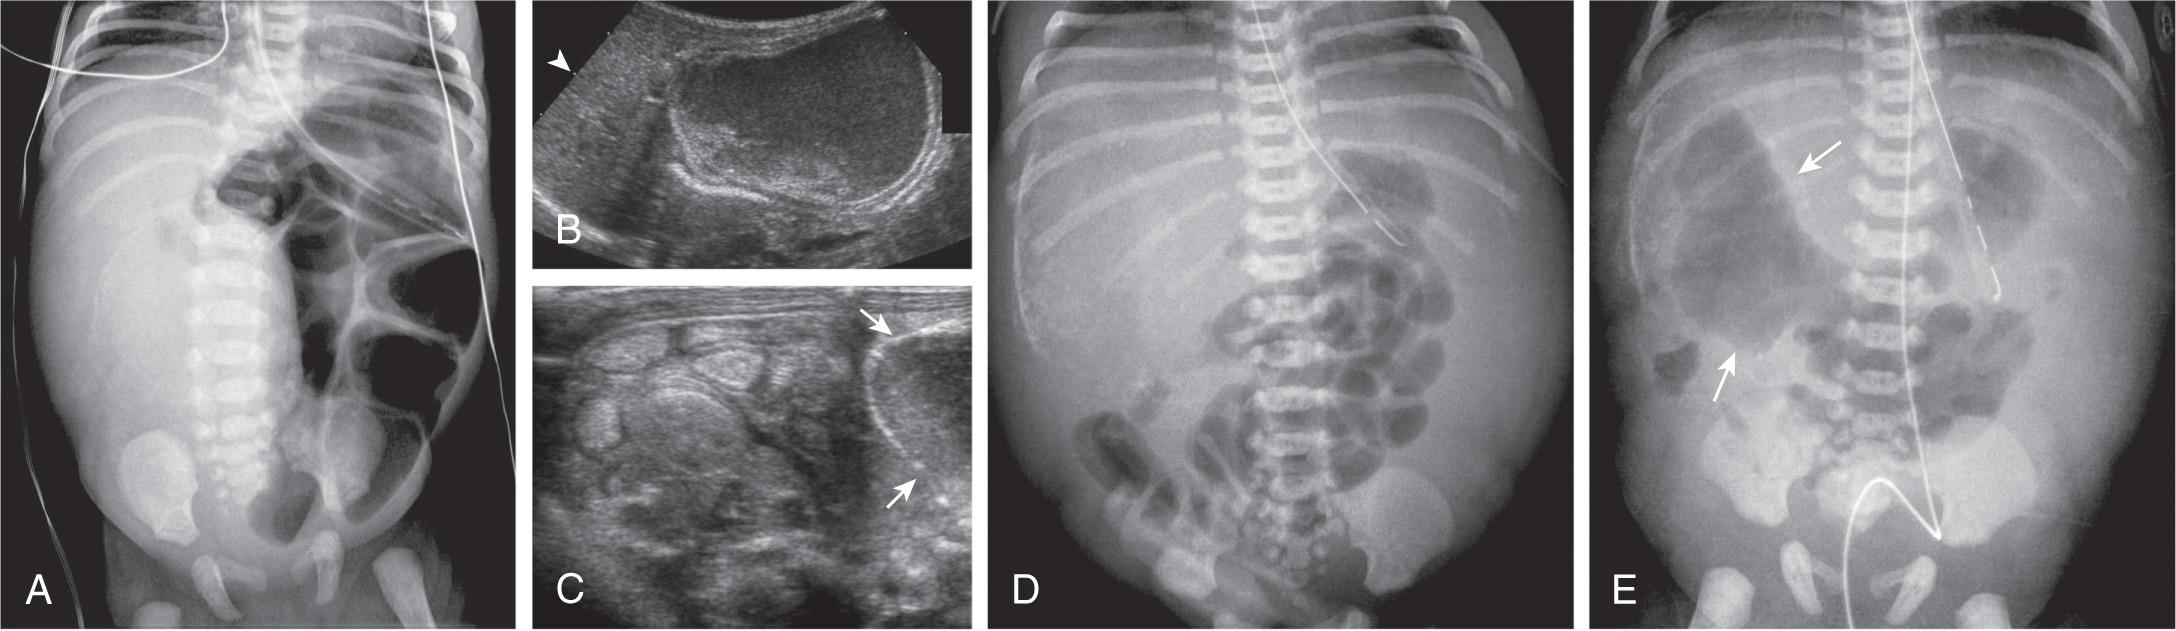

Cases at the most severe end of the spectrum may be diagnosed on prenatal ultrasound with fetal ascites, polyhydramnios, bowel dilation, intraabdominal calcifications, and hydrops fetalis ( Fig. 123.4 ). At the other end are cases in which an intestinal perforation may seal spontaneously and patients remain asymptomatic, except when meconium becomes calcified and is later discovered on radiographs. Alternatively, the clinical picture may be dominated by signs of intestinal obstruction (as in meconium ileus) with abdominal distention, vomiting, and absence of stools or chemical peritonitis presenting with sepsis. Treatment consists primarily of elimination of the intestinal obstruction and drainage of the peritoneal cavity with a timely surgical intervention proved to result in high survival rate and favorable outcome even in complicated meconium peritonitis.

Fig. 123.4, Complicated meconium ileus.

A very high index of suspicion in treating preterm at-risk infants is crucial. Plain abdominal radiographs are essential to make a diagnosis of NEC. The finding of pneumatosis intestinalis (air in the bowel wall) confirms the clinical suspicion of NEC and is diagnostic; 50–75% of patients have pneumatosis when treatment is started ( Fig. 123.5 ). Portal venous gas is a sign of severe disease, and pneumoperitoneum indicates a perforation ( Figs. 123.6 and 123.7 ). Ultrasound with Doppler flow assessment may be useful to evaluate for free fluid, abscess, and bowel wall thickness, peristalsis, and perfusion.

Fig. 123.5, Necrotizing enterocolitis (NEC).

Fig. 123.6, Intestinal perforation.

Fig. 123.7, Necrotizing enterocolitis (NEC).